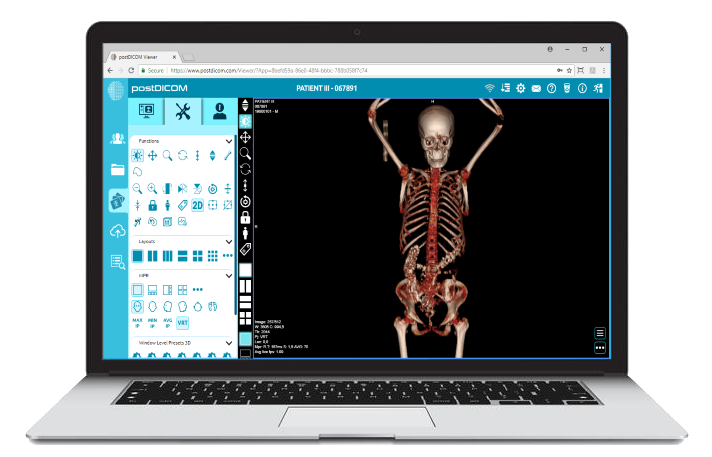

PostDICOM is one of the best DICOM viewers that offers almost all of the above features. It is compatible with Windows, Mac OS X, and Linux. It can be operated from android devices and iOS-based systems. PostDICOM comes with a cloud-based PACS, which allows you to access data from any device, anywhere, at any time. The viewer allows advanced image manipulation, such as 3D reconstruction, 3D volume rendering and MIP, and image fusion. It also offers an interface for creating reports, sharing files, and immediate uploading of all patient data to the cloud PACS.

The cloud-based PACS is unique to this software and offers several advantages. It allows researchers to upload relevant images on the PACS server for viewing, processing, and analyzing at various stages during the course of their clinical research. This ensures complete data integration and a smooth workflow.

Although paid subscriptions are available, the free trial version itself has several premium features. The cloud PACS offers free trial to its paid subscriptions, shares a month, and one or more user logins. These can be increased with different paid subscriptions. PostDICOM offers technical support for the free.